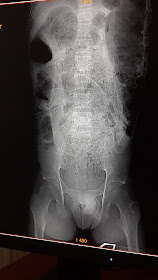

Rx simple d abdomen

La imagen frontal de la TC muestra abundante materia fecal distribuida universalmente en colon

Corte coronal de TC que muestra megacolon a nivel d sigma ocupado

Corte axial d abdomen superior que muestra megacolon ocupado por aire y materia fecal.

Reconstrucción sagital en TC que muestra rectosigma ocupado por contenido fecal.